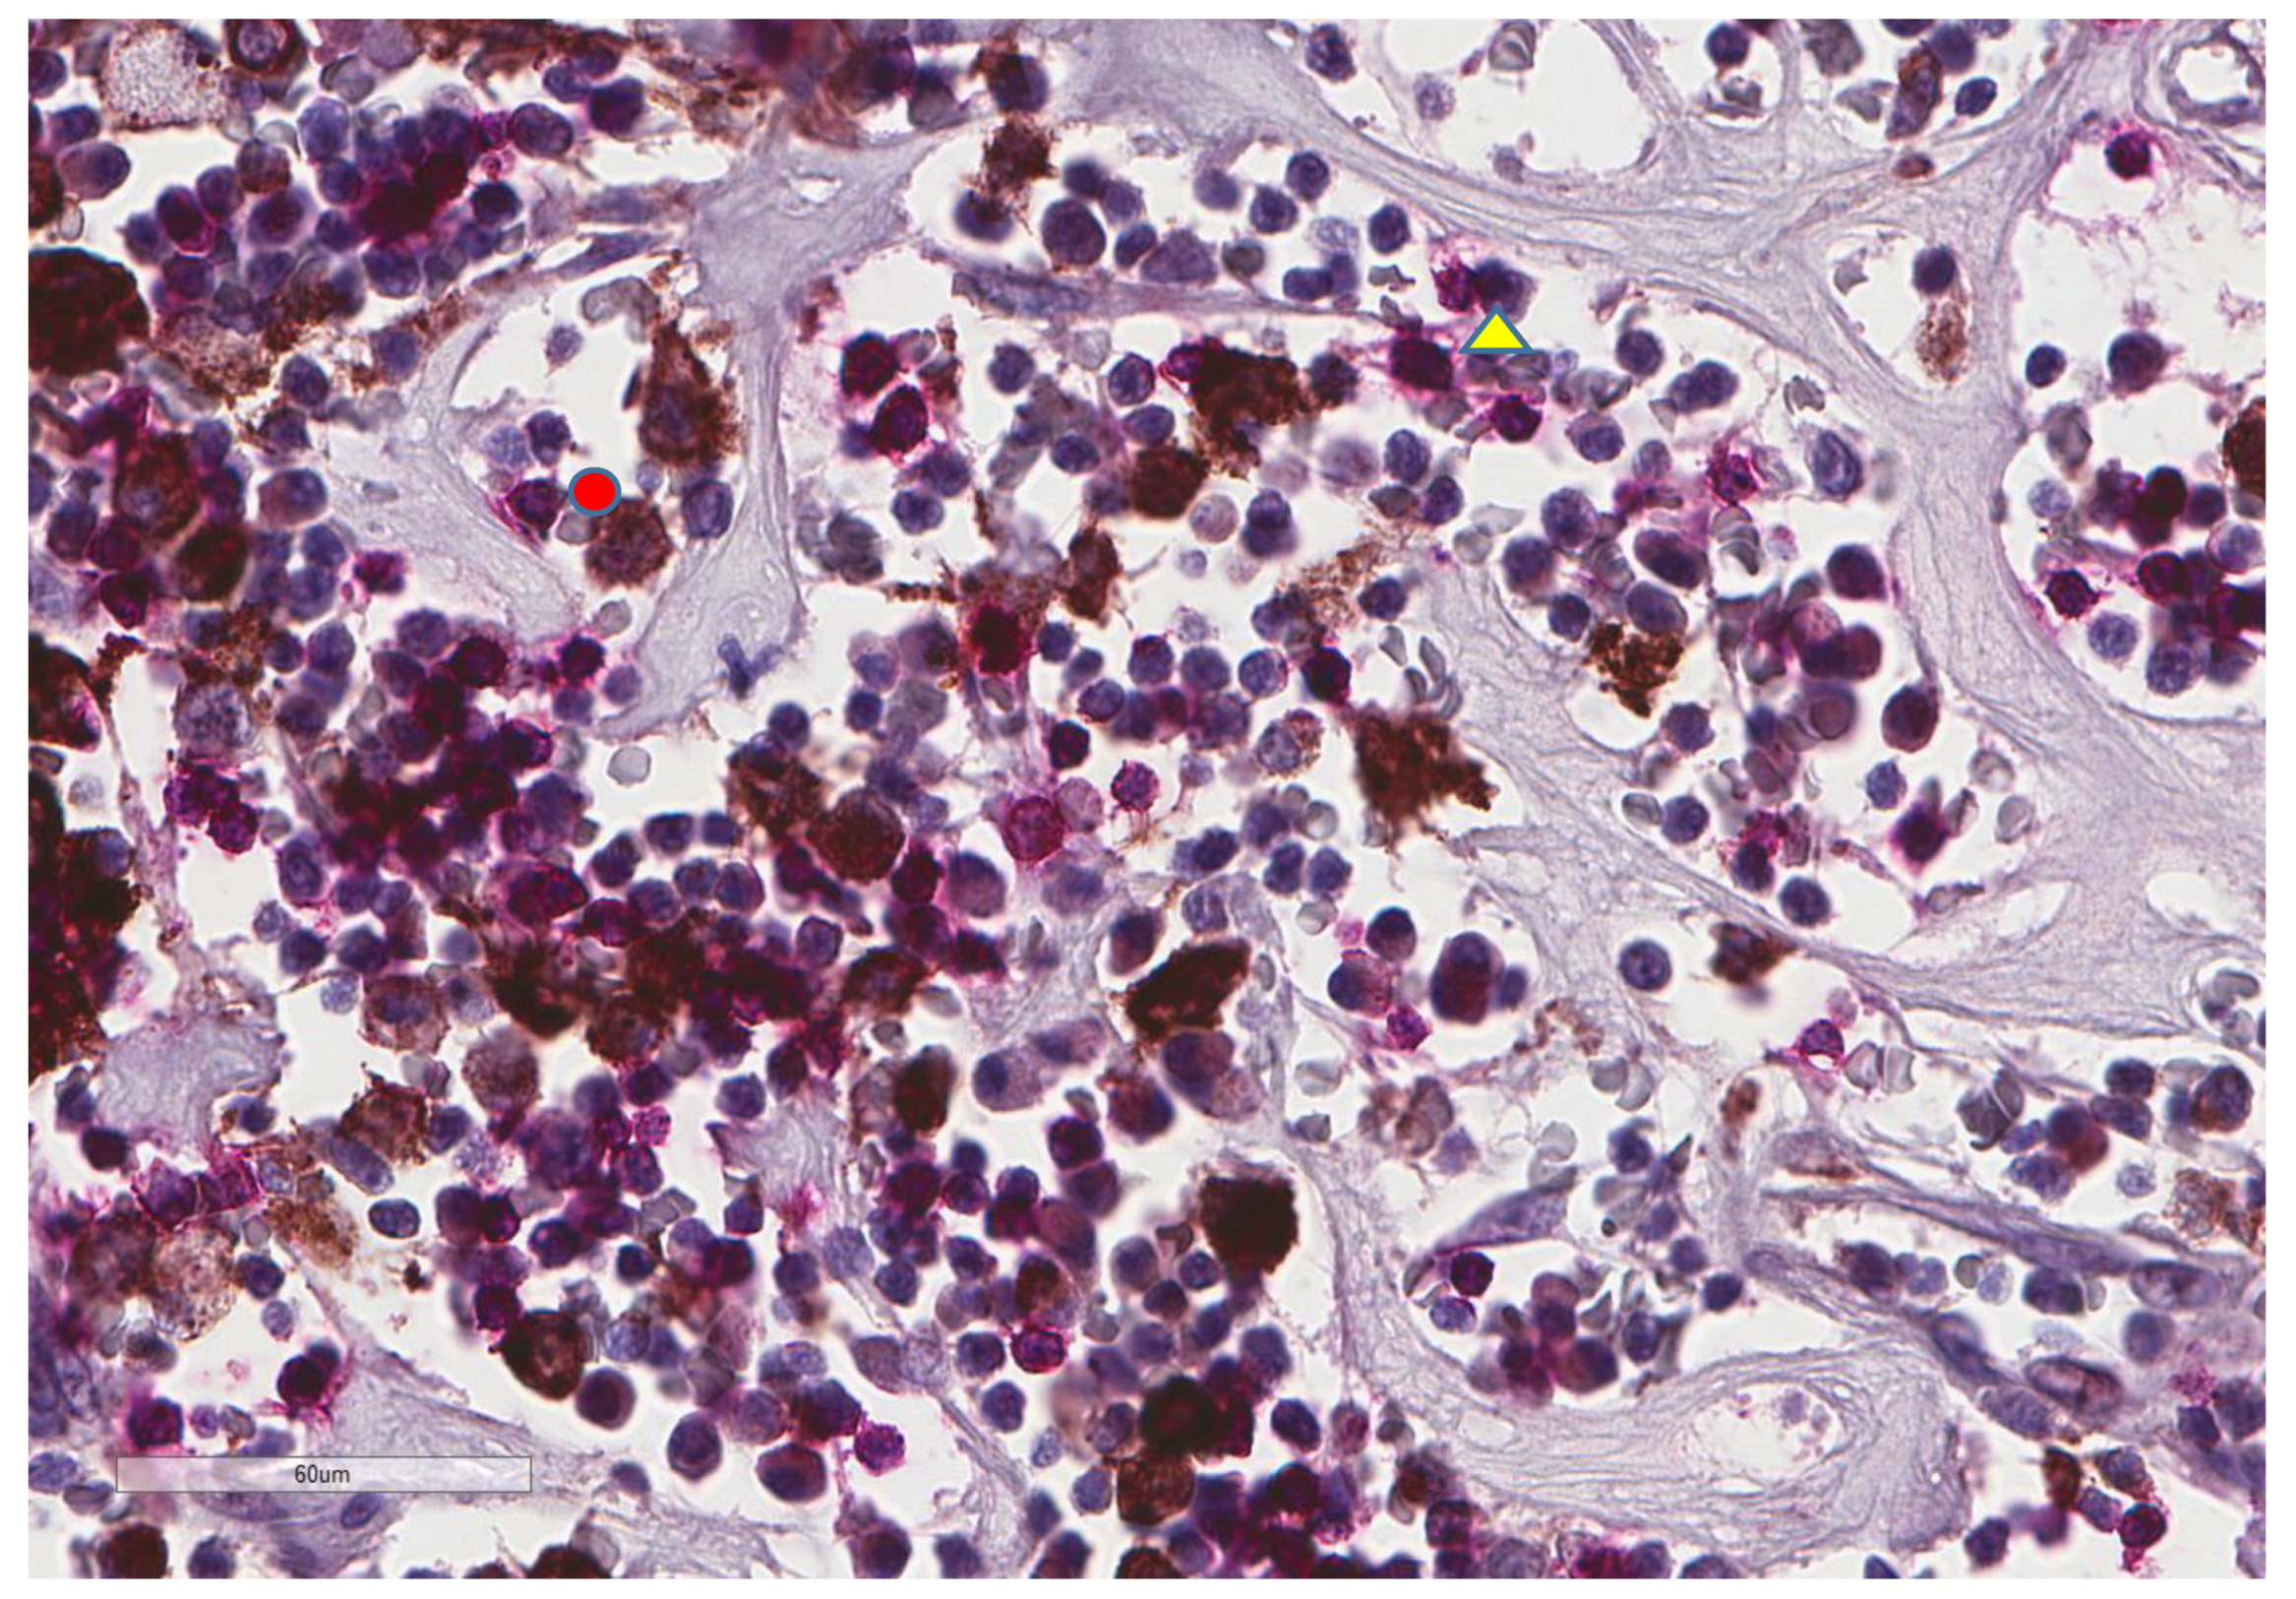

| CD20 (n = 73) | |

| Low (score 0–1) | 65, 89% |

| High (score 2–3) | 8, 11% |

| CD8 (n = 81) | |

| Low (score 0–1) | 55, 67.9% |

| High (score 2–3) | 26, 32.1% |

| CD4 (n = 41) | |

| Low (score 0–1) | 25, 61% |

| High (score 2–3) | 16, 39% |

| CD163 (n = 74) | |

| Low (score 0–1) | 45, 60.8% |

| High (score 2–3) | 29, 39.2% |

| PD-L1 inflammatory cells (n = 81) | |

| No (score 0) | 60, 74% |

| Yes (score 1–3) | 21, 26% |